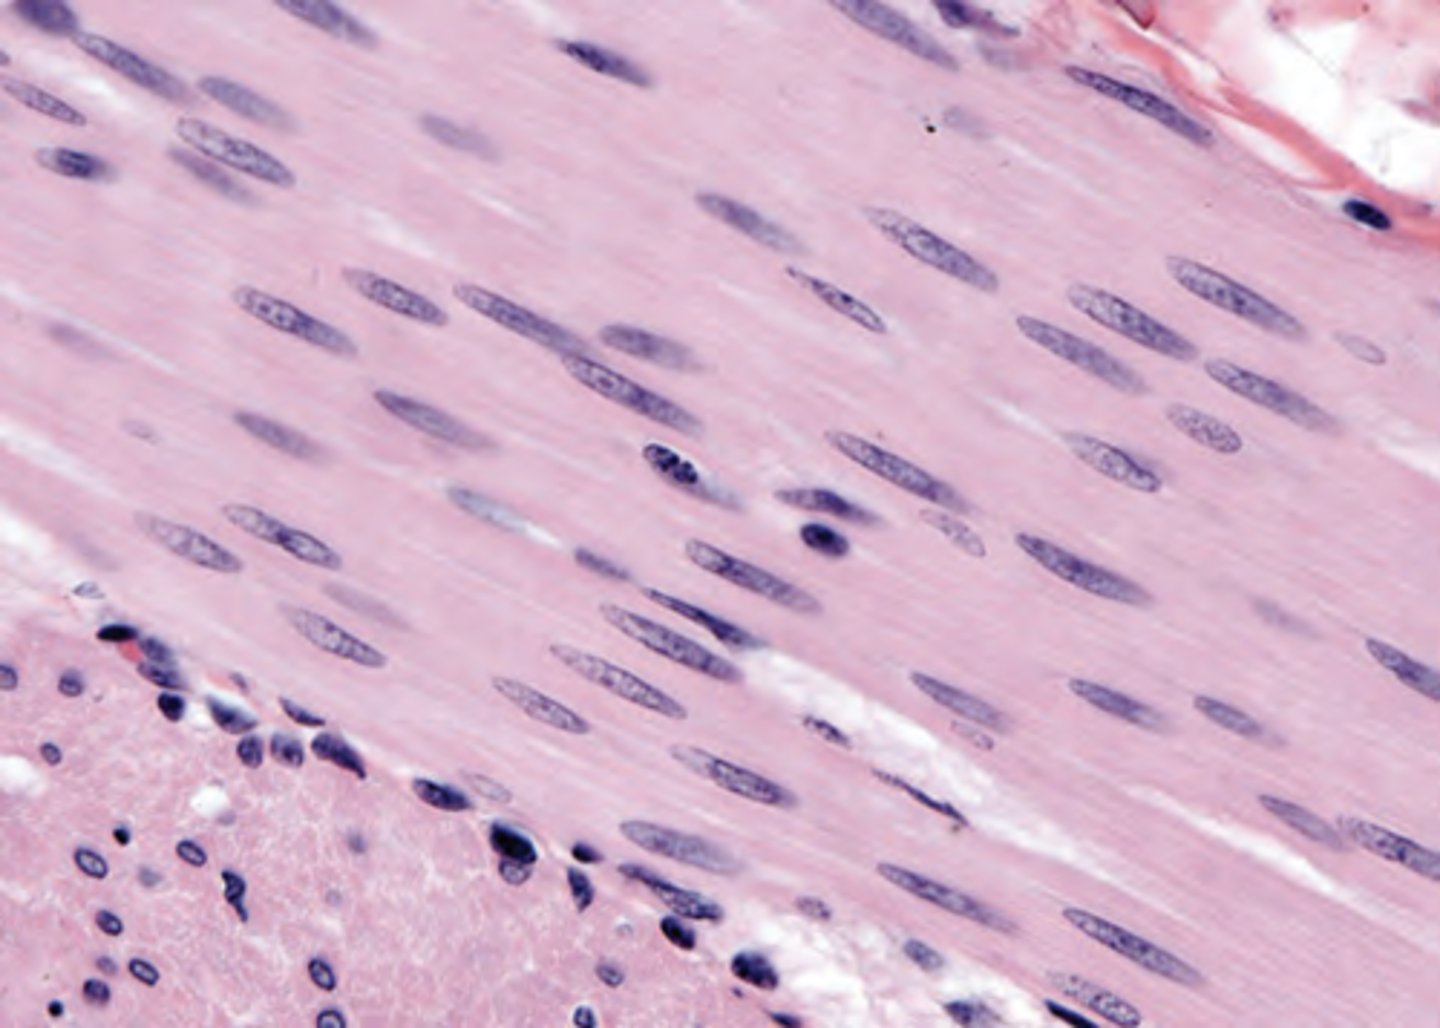

The myocardium of a woman who died of a cardiac arrhythmia is examined in the pathology department (shown in the image). Which of the following statements describes an important feature of cardiac muscle that helps distinguish cardiac from skeletal muscle in routine H&E slide preparations?

(A) Connective tissue contains a rich capillary network.

(B) Muscle fibers are composed of multiple cells.

(C) Muscle fibers exhibit cross-striations.

(D) Sarcomeres are located between adjacent Z lines.

(E) Thin filaments contain actin.

The answer is B. Unlike skeletal muscle, where muscle fibers are multinucleated cells, cardiac muscle fibers are composed of multiple cells that make tight end-to-end connections. Cardiac muscle cells may split and unite, giving cardiac muscle a typical "branching" morphology. Cardiac and skeletal muscles both exhibit cross-striations—their thick and thin contractile filaments exhibit the same organization (choices C, D, E). The nuclei of cardiac and skeletal muscle are, however, distinctly different. The nuclei of skeletal muscle cells are located at the periphery of the fiber, whereas the nucleus of a cardiac myocyte is located in the center of the cell (shown in the image). This difference in nuclear location provides a useful means for distinguishing cardiac from skeletal muscle. Cardiac and skeletal muscle fibers are both invested with connective tissue that conveys nerves and capillaries (choice A).